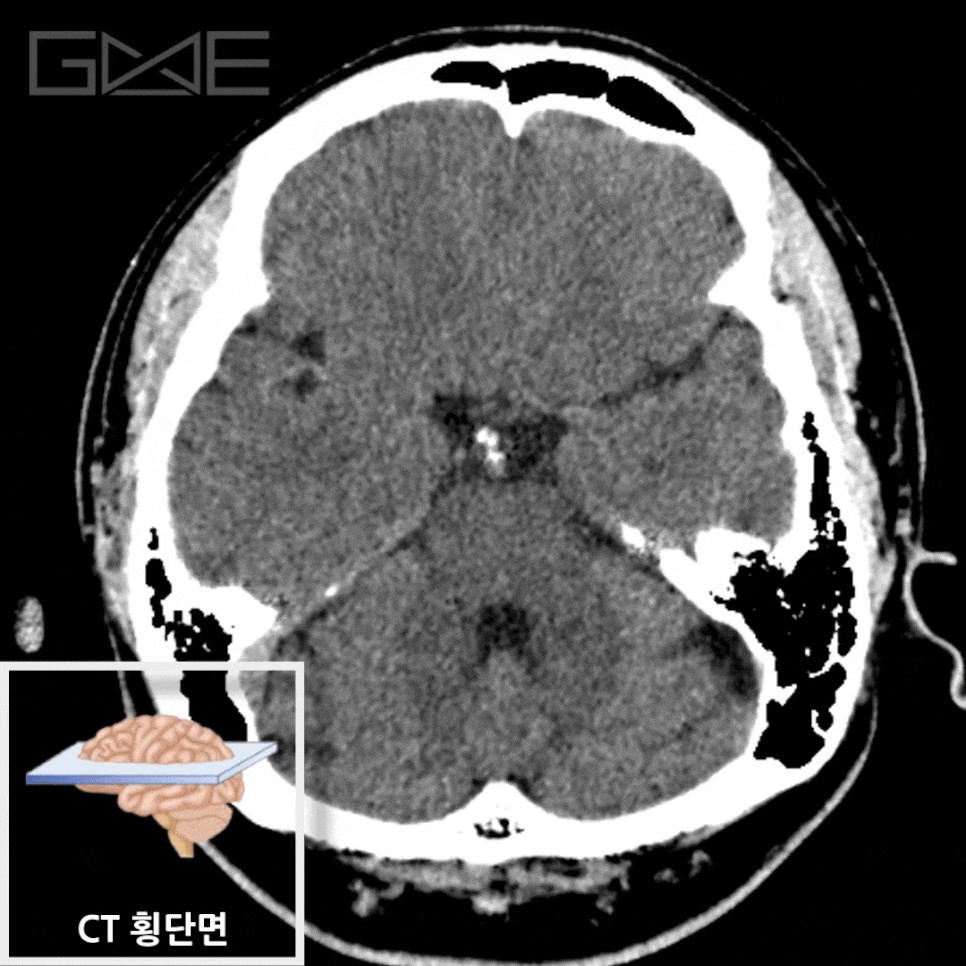

Brain CT

Principle

– X선 감쇠 차이를 단층 영상으로 재구성

– 임상 필요 시 조영제를 사용하여 혈관·종양 평가(CTA/CTV 포함)

Key Features

– 촬영이 매우 빠르고 출혈 탐지에 우수

– 방사선·요오드 조영제 노출

– 허혈 초기 병변은 민감도가 제한되어 추가 MRI가 필요할 수 있음